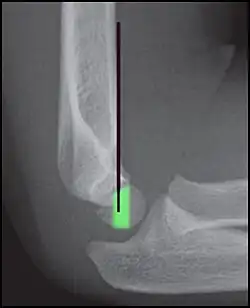

Anterior humeral line (black line), with normal area passed on the capitulum of the humerus colored in green in a 4-year-old child.[9]

The anterior humeral line is not reliable in children with sparse ossification of the capitulum, such as in this 6 months old child.[9]